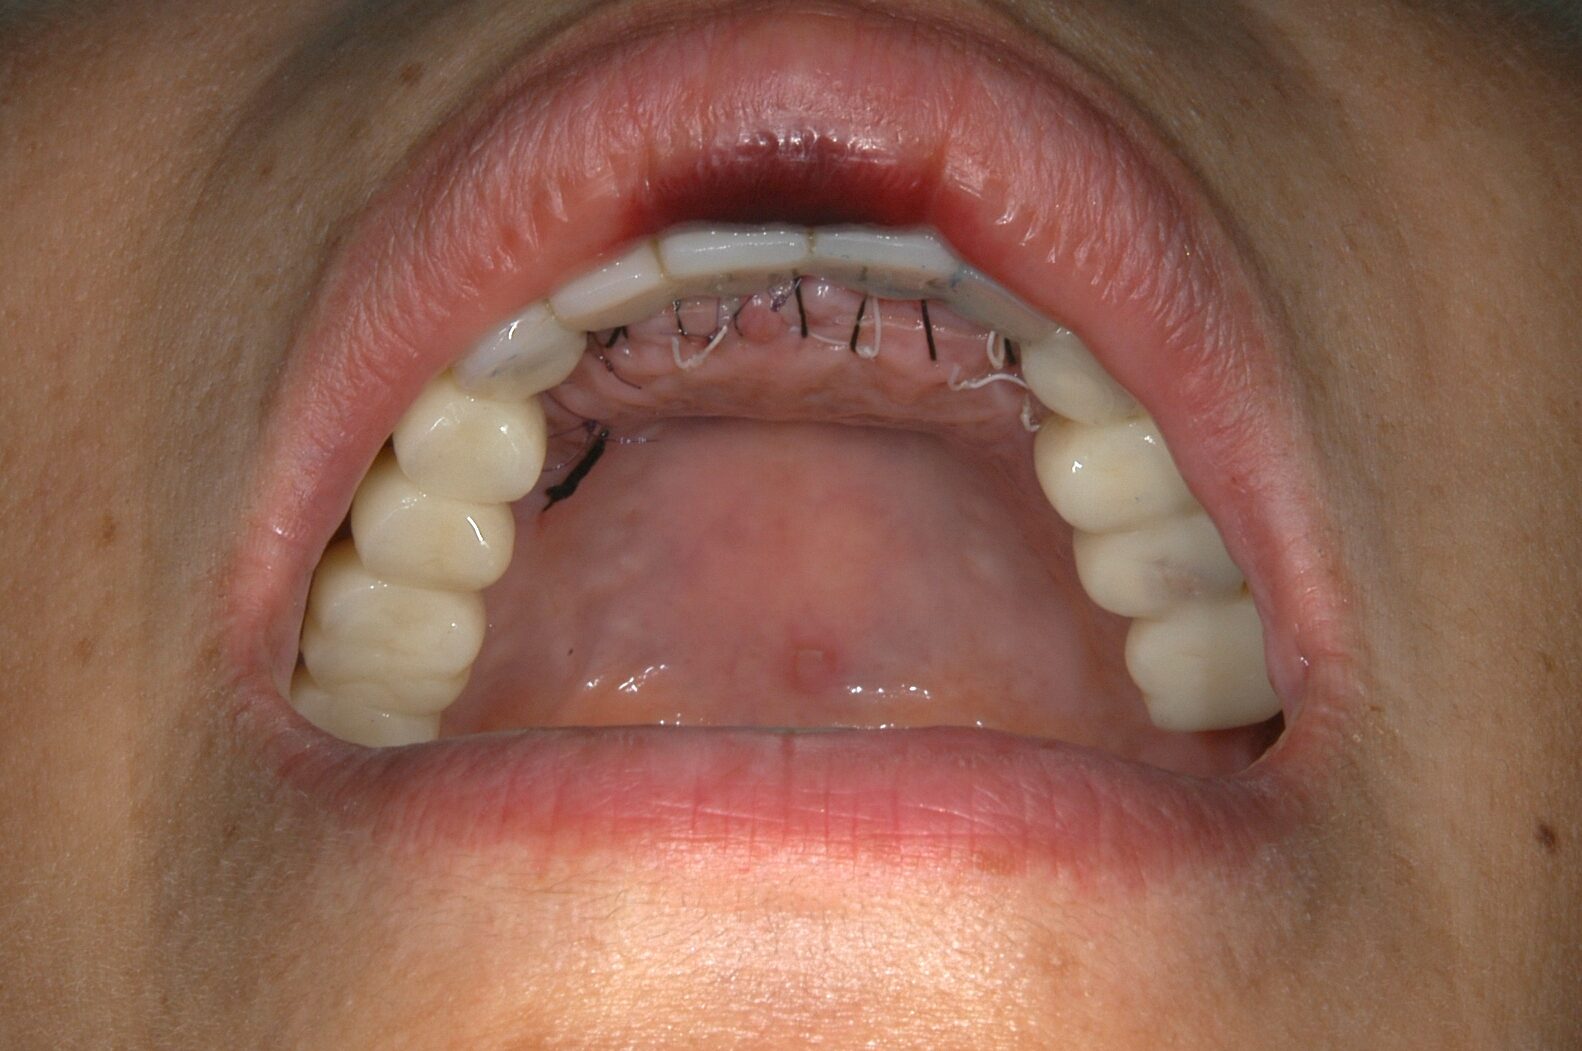

治療④ 上の前歯の被せ物

実際にお口の中にSETした写真になります